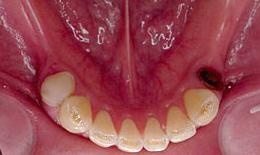

インプラント症例(1)30代 女性

治療前

上顎

保存困難な歯を抜歯後、インプラントを7本埋め込み、セラミックスクラウンを被せた

下顎

保存困難な歯を抜歯後、インプラントを6本埋め込み、セラミックスクラウンを被せた